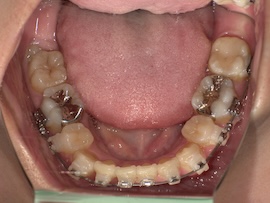

前回から1ヶ月後の歯並びはこんな感じです。

左上親知らずの牽引を始めてたった1ヶ月ですが、かなり出てきている気がします。

内側の装置は汚れが溜まりやすいのか前歯との間の歯肉が腫れ痛みが出ることが時々ありました。話しづらさ等の違和感はもう全くありません。